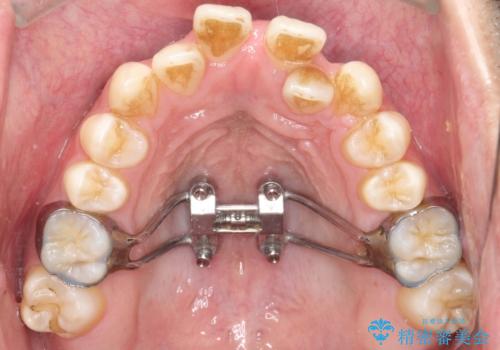

- MSE+インビザライン

上の歯のアーチが狭窄していたため、骨の幅を広くするためにMSE(急速拡大装置)を使用してからインビザライン にて治療を行いました。

MSE(急速拡大装置)を用いたことで、短期間で奥歯の噛み合わせもしっかりと治すことができました。